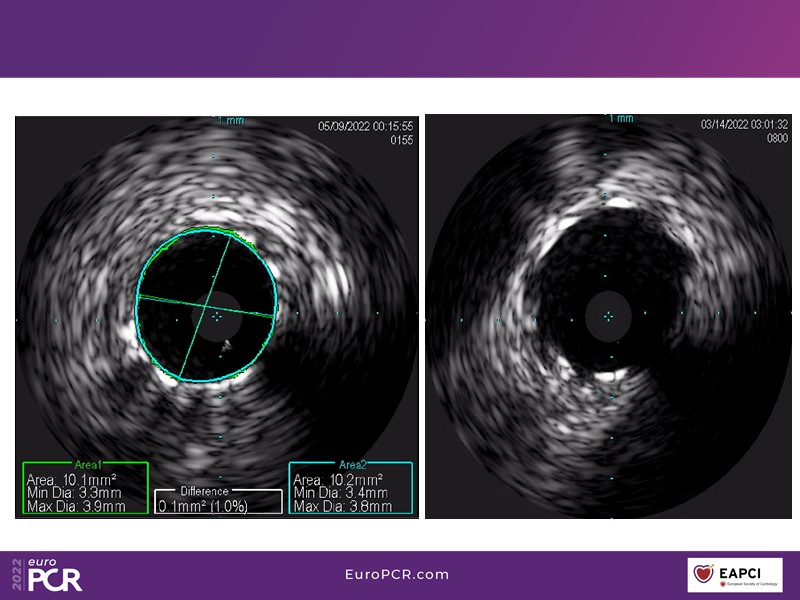

Alexandre Abizaid, Marco Valgimigli, Fazila Malik, Luca Testa, Patrick W. Serruys, Damiano Regazzoli, Kumar Prathap, and Sandeep Basavarajaiah take turns in this session to discuss two innovative technologies: a stent platform with nanotechnology and a novel drug-coated balloon (DCB). These novel technologies both have unique features that could change daily practice and improve outcomes.

- To find out more about the application and mechanism of a sirolimus coated balloon for coronary artery disease treatment with case presentations in complex settings

- To understand how useful is a DES and DCB stent platform in complex coronary artery disease settings with case demonstrations and follow-up in diabetes mellitus